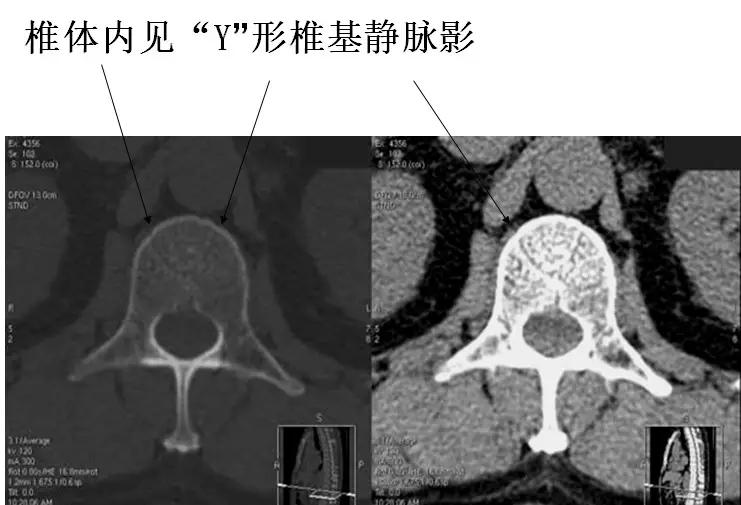

椎基静脉影

椎间孔前为椎体,后为椎小关节,上下为椎弓根,内与侧隐窝相连,有脊神经根通过。

侧隐窝:向下外续于椎间孔,有脊神经经过:前壁为椎体后外缘;后壁为上关节突前面与黄韧带;外界为椎弓根。

正常前后径为3-5mm,<3mm侧隐窝狭窄>5mm,肯定不狭窄。